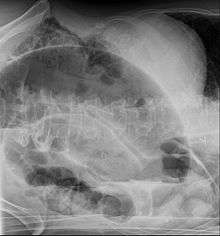

After taking a thorough history, the diagnosis of colonic volvulus is usually easily included in the differential diagnosis. Abdominal plain x-rays are commonly confirmatory for a volvulus, especially if a "bent inner tube" sign or a "coffee bean" sign are seen. These refer to the shape of the air filled closed loop of colon which forms the volvulus. Should the diagnosis be in doubt, a barium enema may be used to demonstrate a "bird's beak" at the point where the segment of proximal bowel and distal bowel rotate to form the volvulus. This area shows an acute and sharp tapering and looks like a bird's beak. If a perforation is suspected, barium should not be used due to its potentially lethal effects when distributed throughout the free infraperitoneal cavity. Gastrografin, which is safer, can be substituted for barium.

- Abdominal x-ray – tire-like shadow arising from right iliac fossa and passing to left